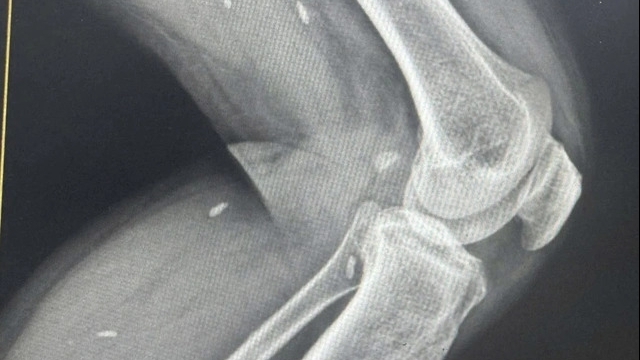

![]() |

| Cắt cụt 1/3 trên cánh tay trái, giữ mỏm cụt để cứu sống người bệnh. Ảnh: Bệnh viện Bạch Mai. |

Không ai muốn người bệnh mất đi một phần cơ thể nhưng nếu chần chừ, cái giá phải trả có thể là cả một sinh mạng. Các bác sĩ buộc phải đối mặt với lựa chọn khó khăn: Cắt cụt 1/3 trên cánh tay trái để cứu sống người bệnh.